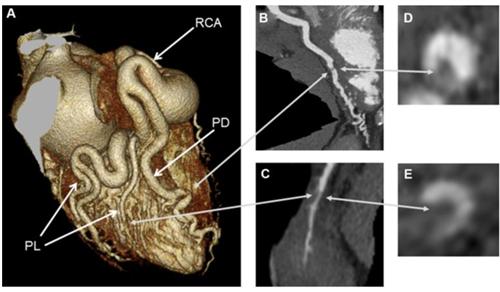

冠状动脉起源于肺动脉是指一支冠状动脉或其分支(左前降冠状动脉或左回旋冠状动脉),或两支冠状动脉起源于近端肺动脉干,或极少数起源于近端右肺动脉。冠状动脉异常起源于肺动脉是什么?接下来跟大家分享下我的看法。

冠状动脉的正常发育必须由主动脉窦长出冠状动脉芽,并于心外膜下冠状动脉血管丛连接,心外膜下血管丛是与静脉结构形成的心肌内血管丛交通。在正常发育过程中,肺动脉干也长出冠状动脉芽,但通常退化消失,左或右冠状动脉丛未与主动脉窦芽连接,而与肺动脉芽异常连接,则形成冠状动脉异常起源于肺动脉。